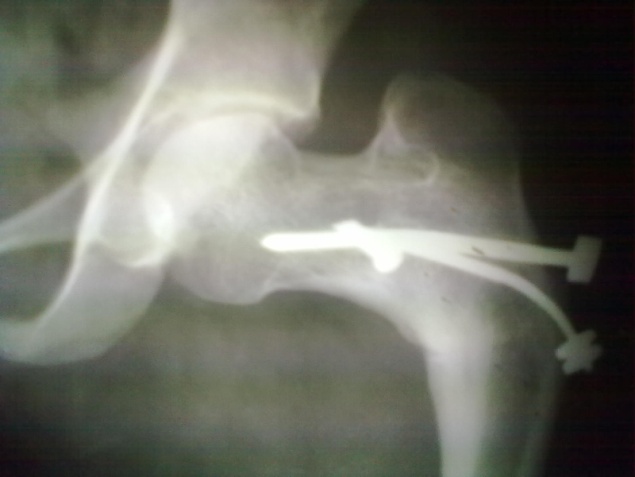

Spinal block was used in the procedure. Prone position on fracture table with radiolucent top was used. Fracture site was exposed through posterior approach and sclerosed margins of the fragments were freshened. Fracture was reduced with appropriate neck shaft angle and fixed with Moors pin/ knowels pin or 4 mm /7mm partially threaded cancellous screws. Any rotation or tilt was corrected. The fixation was augmented with quadratus femoris muscle pedicle bone graft harvested from intertochateric crest area with a bone pedicle of length 2 cm, width 1 cm and depth 1 cm. The graft was secured to the proximal femoral head fragment with 3.5mm cortical screw or 4mm cannulated cancellous screw. Soft tissue closure was done over drain.